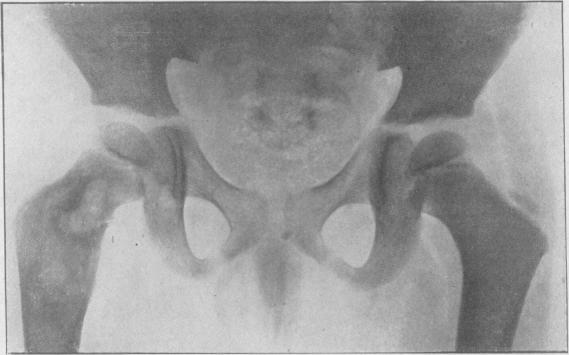

ARDEN G P

Proc R Soc Med. 1949 Feb;42(2):94. doi: 10.1177/003591574904200231.